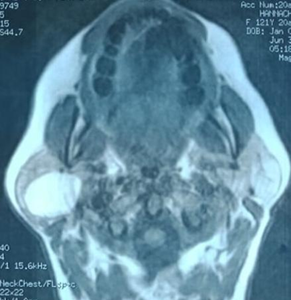

On magnetic

resonance imaging (MRI), a 31x26x30 mm oval-shaped lesion with well-defined

contours was identified in the inferior part of the superficial lobe of the

right parotid gland. It was partially extended to the

deep lobe. The lesion exhibited homogeneity and very high intensity on

T1-weighted images, high intensity on T2-weighted images, and low intensity on

diffusion-weighted images. The lesion was not enhanced after gadolinium

injection. This intensity pattern was identical to that of the fatty tissue (Figure 2).

Therefore,

the images suggested the diagnosis of parotid lipoma.

Figure 2. MRI images

show the fatty mass in the right parotid gland.